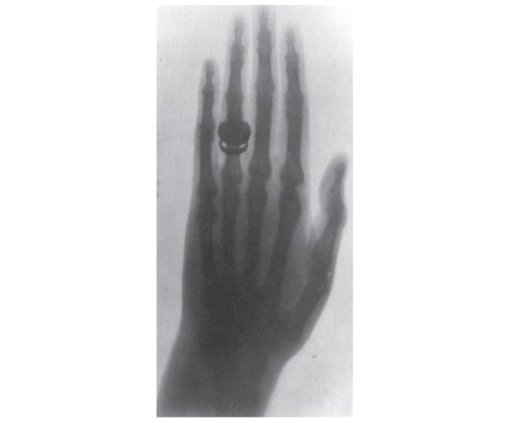

Brogdon e Brecher (2011, p.12) (Imagem 1) relatam:

George Holder disparou a sua arma sobre a perna de Tolson Cunning. Várias tentativas foram realizadas para tentar localizar o projéctil, mas resultaram todas em infortúnios. A ferida cicatrizou, mas o senhor Cumning persistiu com a sintomatologia. A pedido do médico da vítima, um professor de Física da Universidade de McGill, James Cox realizou uma radiografia da extremidade ferida. Num anfiteatro de Física todo o material foi disponibilizado, e no final de 45 minutos de exposição a “fotografia” mostrava um projéctil achatado “enclausurado” entre a tíbia e o perónio. Tolson Cumning foi então sujeito a uma intervenção cirúrgica.

Imagem 1 - A perna de Tolson Cunning foi submetida a um exame de raios X para localizar o projétil disparado por George Holder na véspera de Natal de 1895. O exame foi realizado no Laboratório de Física da Universidade McGill, em Montreal, em 7 de fevereiro de 1896. O resultado foi a primeira placa de raio-X a ser admitida em um tribunal na América do Norte (Brogdon, 2011, p.13).